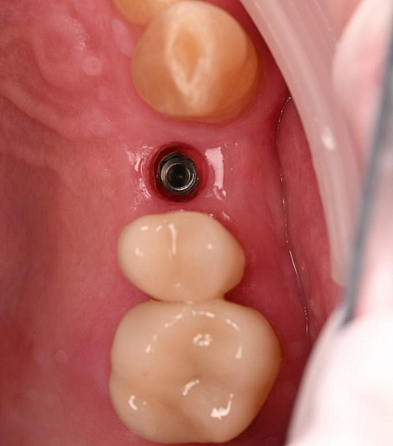

Three months after the implant surgery, a thorough post-operative assessment revealed excellent healing and implant stability.

Digital impressions were captured using the TRIOS 4 intraoral scanner, and the implant-supported crown was designed using 3Shape Design Studio.